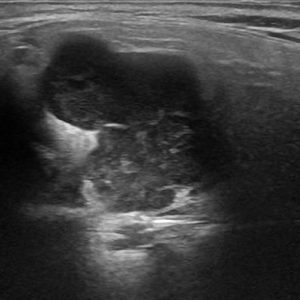

U tuyến nước bọt

Lượt xem: 170» 17-01-2021 -

U tuyến nước bọt

Lượt xem: 174» 17-01-2021 -

U tuyến nước bọt

Lượt xem: 149» 17-01-2021 -

U tuyến nước bọt

Lượt xem: 147» 17-01-2021 -

U tuyến nước bọt

Lượt xem: 146» 17-01-2021 -

U tuyến nước bọt

Lượt xem: 151» 17-01-2021 -

U tuyến nước bọt

Lượt xem: 146» 17-01-2021 -

U tuyến nước bọt

Lượt xem: 136» 17-01-2021 -

U tuyến nước bọt

Lượt xem: 132» 17-01-2021 -

U tuyến nước bọt

Lượt xem: 209» 17-01-2021 -

U tuyến nước bọt

Lượt xem: 150» 17-01-2021 -

U tuyến nước bọt

Lượt xem: 185» 17-01-2021 -

U tuyến nước bọt

Lượt xem: 151» 17-01-2021 -

U tuyến nước bọt

Lượt xem: 212» 17-01-2021 -